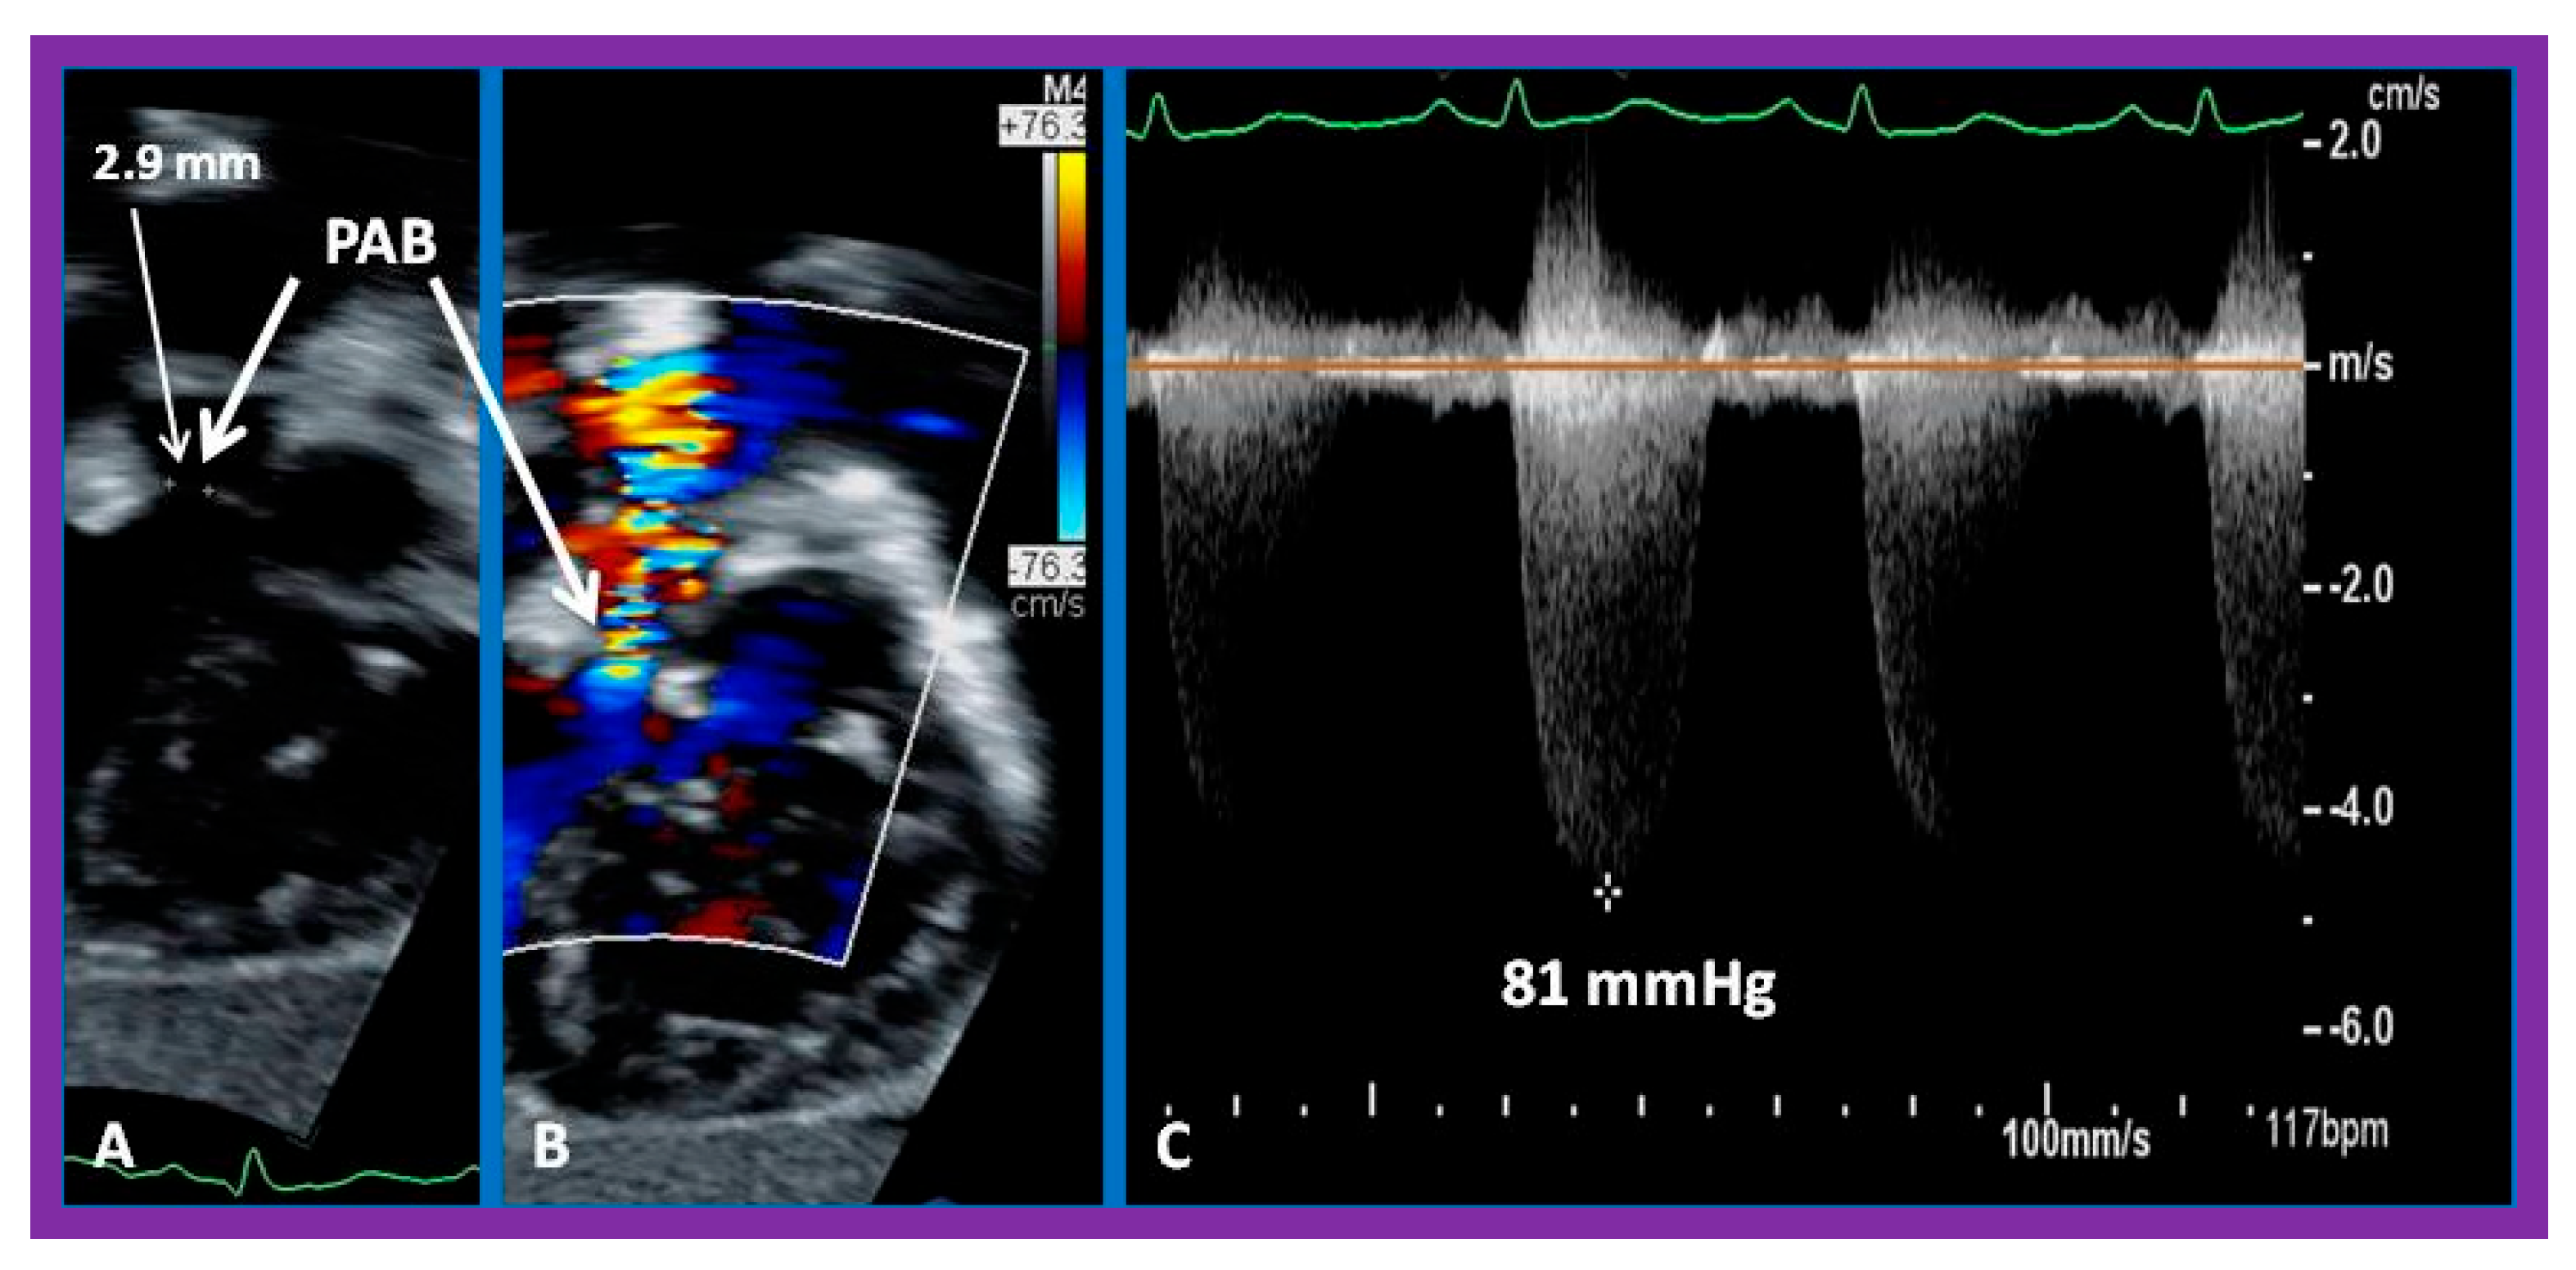

- Muller, W.H., Jr.; Danimann, J.F., Jr. The treatment of certain congenital malformations of the heart by the creation of pulmonic stenosis to reduce pulmonary hypertension and excessive pulmonary blood flow, a preliminary report. Surg. Gynecol. Obstet. 1952, 95, 213–219. [Google Scholar]

- Afifi, A.R.S.A.; Seale, A.N.; Chaudhari, M.; Khan, N.E.; Jones, T.J.; Stumper, O.; Botha, P. Pulmonary artery banding: Still a role for staged bi-ventricular repair of intracardiac shunts? Cardiol. Young 2022, 14, 1–7. [Google Scholar] [CrossRef]

- Agasthi, P.; Graziano, J.N. Pulmonary Artery Banding. 1 October 2022. In StatPearls; StatPearls Publishing: Treasure Island, FL, USA, 2023. [Google Scholar]